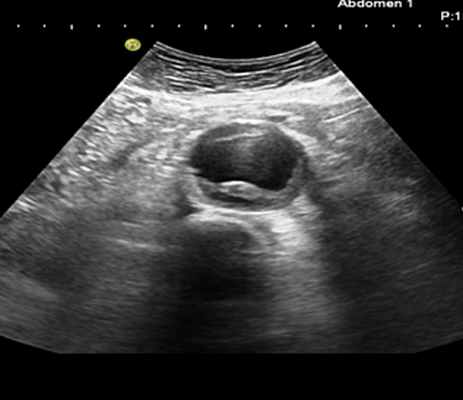

При расслоении III типа проводится УЗИ брюшной аорты.

Поэтому для уточнения патологии, пока она не «разродилась» опасными усложнениями, применяют инструментальные методы диагностики: рентгеноскопия и рентгенография грудной клетки и брюшной полости — при них визуализируется опухолевидное образование (его пульсацию видно при рентгеноскопии); эхокардиография — при подозрении на аневризму восходящей аорты; ультразвуковая допплерография (УЗДГ) — при признаках аневризмы других участков аорты; КТ и МРТ.